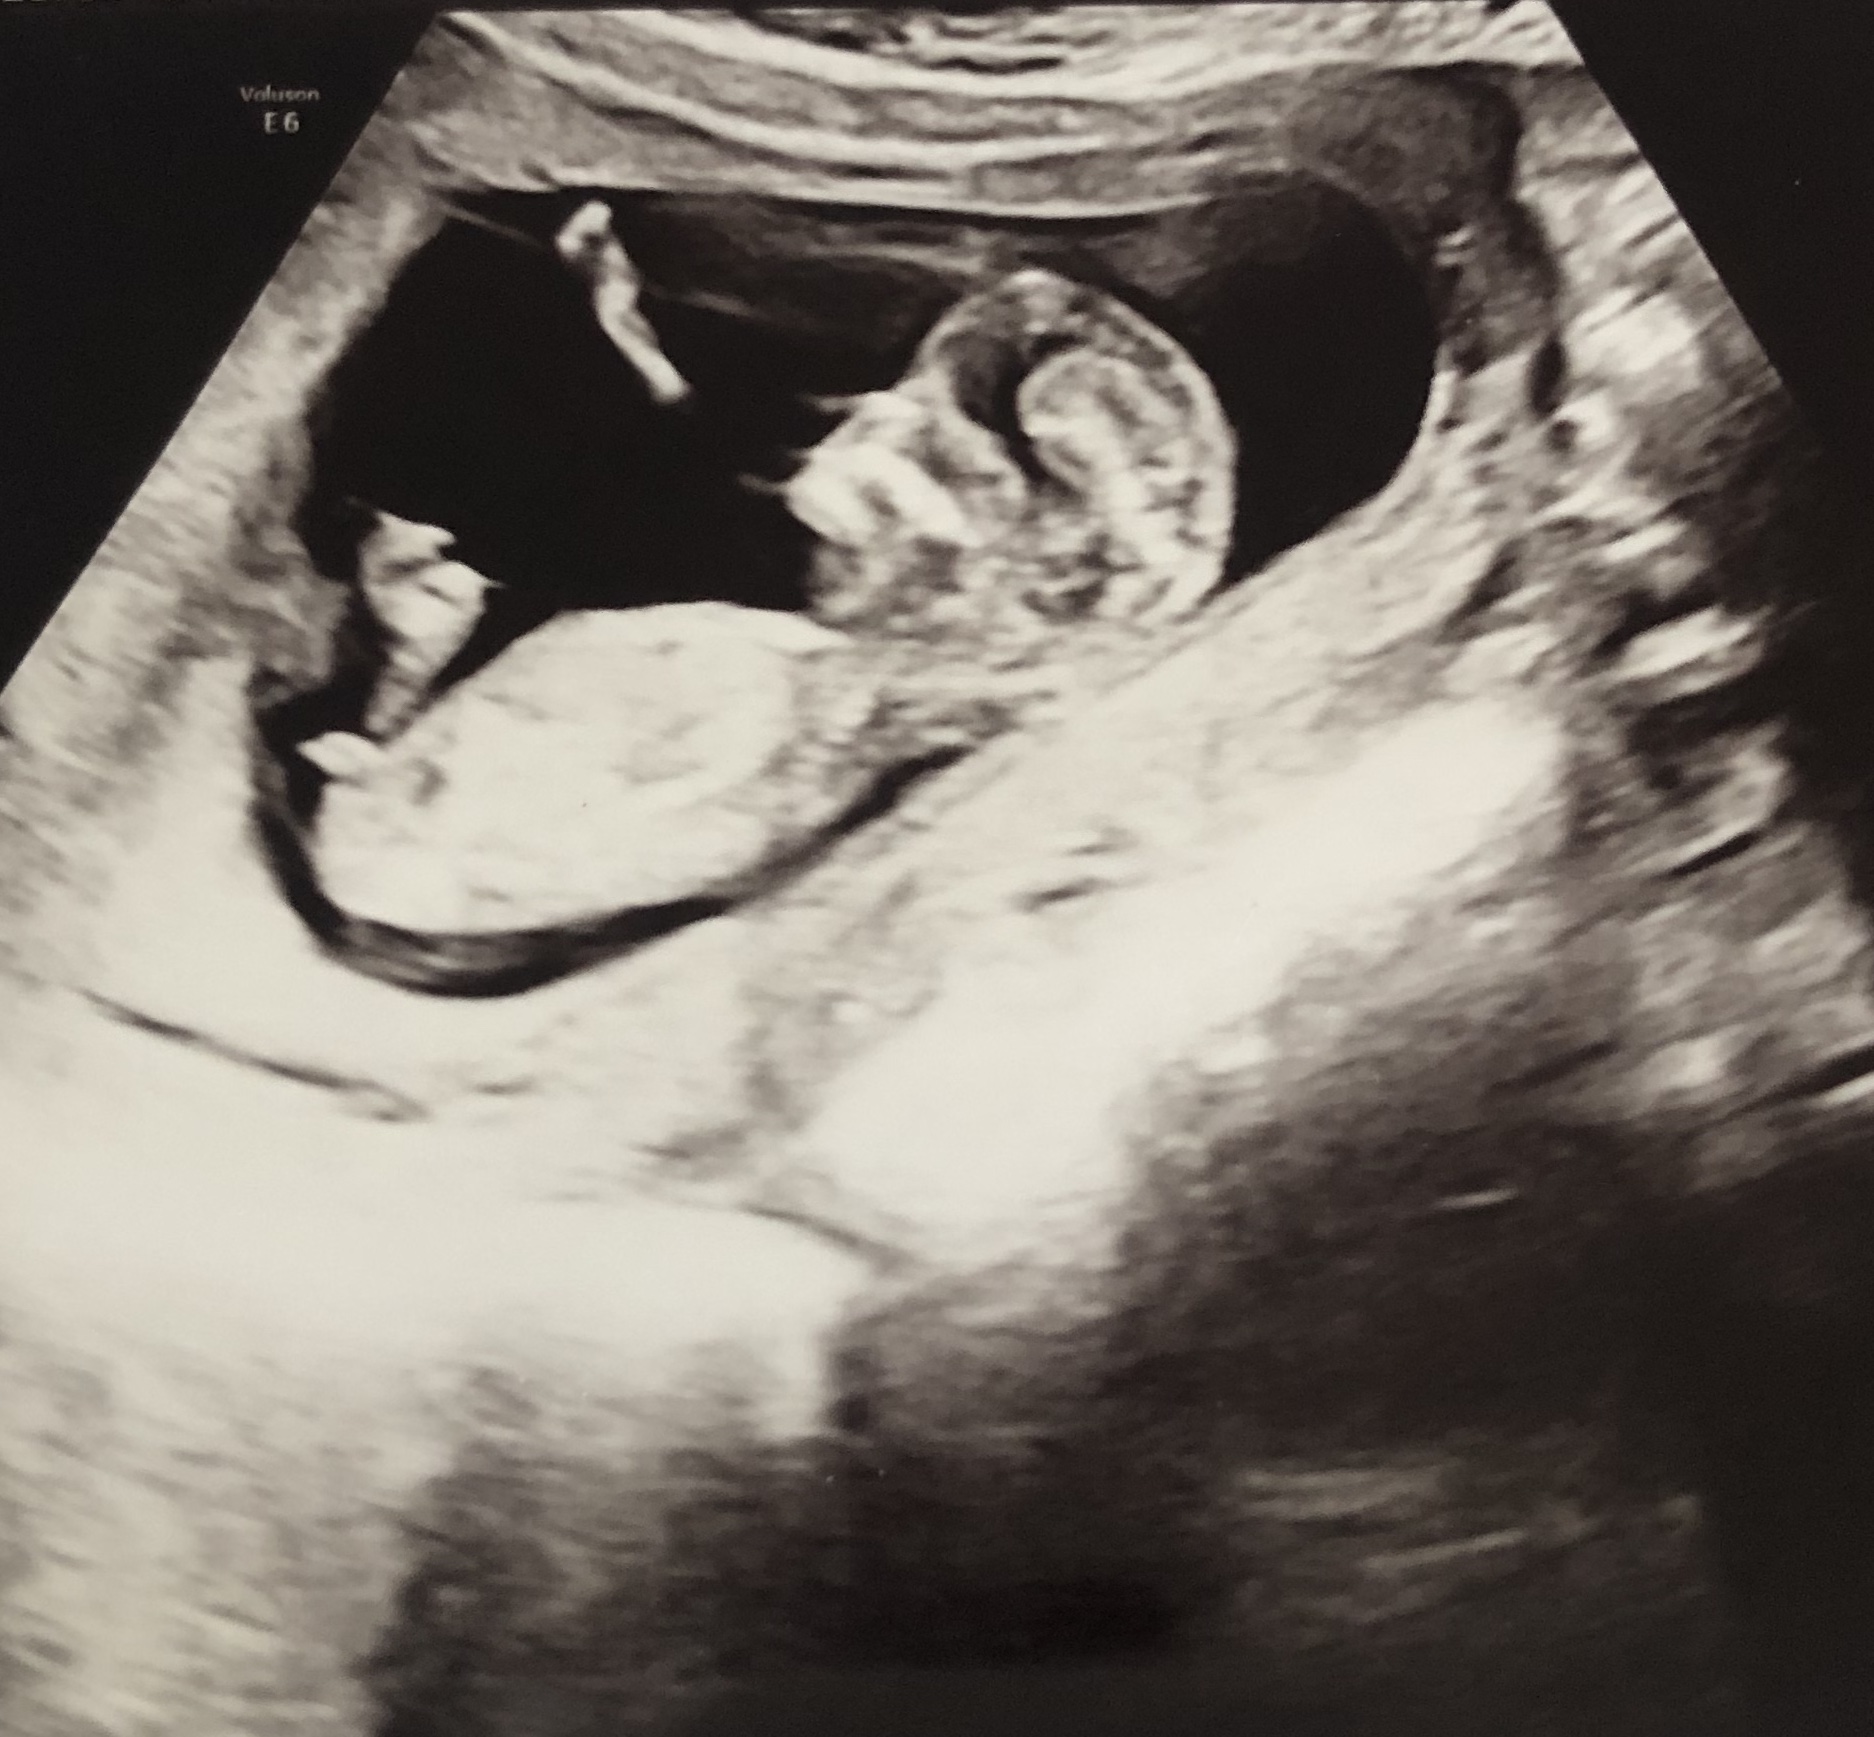

מבינות באולטסאונד? בן או בת..._shira_

מה הרופא אמר? אפילו לרופאים קשה להבחין באולטרסאונדבתי 123

הרופא אמר שזה לא ברור אבל אולי בת

אי אפשר לדעת מהתמונהבאורות

זאת לא התנוחה הנכונה לבדוק מין עוברשירוש16אחרונה